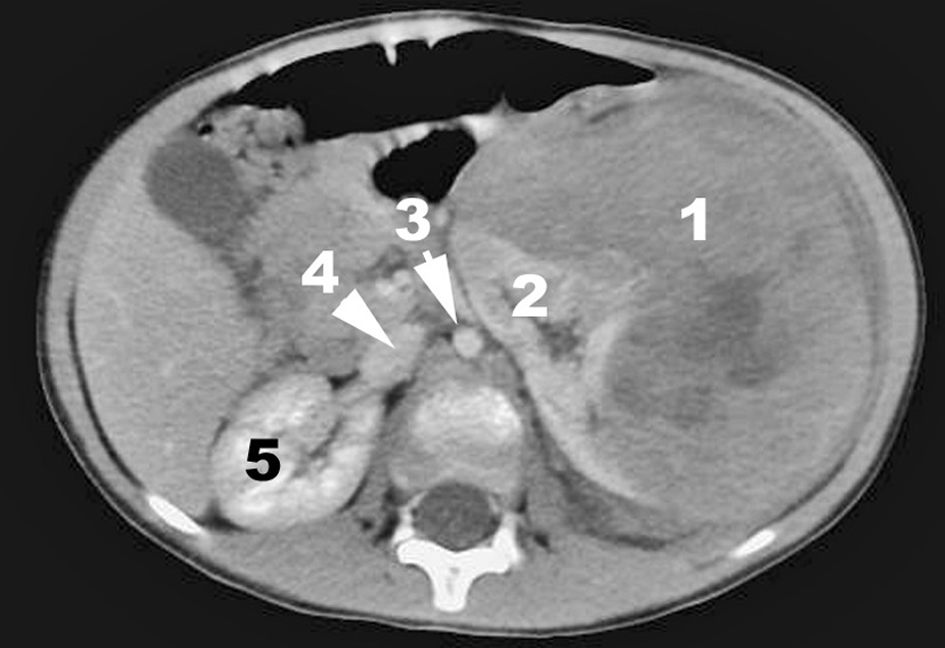

L’IRM ou la TDM (avec injection) précise l’origine anatomique de la tumeur (intra- ou extrarénale), ses rapports avec les organes voisins et avec les principaux vaisseaux. Elle recherche des anomalies locorégionales comme des adénopathies ou une seconde localisation (figures 105.3 et 105.4).

Fig. 105.3 Exemple de néphroblastome en tomodensitométrie.

La tumeur, partiellement nécrosée (1), est enchâssée dans le rein gauche (2). Autres structures : aorte (3), veine cave inférieure (4), rein droit (5).

Source : CERF, CNEBMN, 2022.